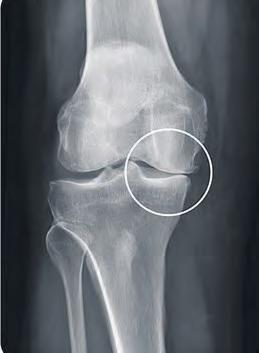

Wann die OP ratsam ist

Informationen zu Knieverletzungen

H UCKELRIEDE Die Roland Klinik lädt für Mittwoch, 26. April, ab 17.30 Uhr, im Rahmen der reihe „Dialog ... Bewegung“ zu einer Informationsveranstaltung mit dem leitenden Oberarzt im Zentrum für Sporttraumatologie, Christian Homuth, ein. Das Knie ist aufgrund seiner hohen Funktionalität und Komplexität besonders anfällig für Verletzungen. Insbesondere Kontaktsport wie Fuß- oder Handball, aber auch Einzelsportarten wie Tennis oder Laufen können zu Verletzungen rund um das Knie führen – vom Bänderriss über Sehnenverletzungen bis hin zu Knorpelschäden, ob im Leistungsbereich oder im Freizeitsport. Verletzungen an Meniskus, Kreuzband und Knorpel sind sogenannte Dauerschäden. Diese können sich langfristig auf die Arthrose-Entwicklung auswirken und im Laufe des Lebens eine Knieprothese notwendig machen. Wann und

bei welcher Verletzung eine Operation ratsam ist, darüber und zu weiteren Fragen informiert Christian Homuth im Activo an der Roland Klinik, Niedersachsendamm 65a.

Die Zahl der Plätze ist begrenzt, daher wird um Anmeldung wird gebeten. Interessierte können sich am Dienstag, 25. April, ab 9 Uhr telefonisch anmelden unter der Nummer 877 83 30. (rf)